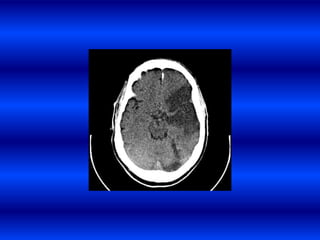

Hemorragia por anticoagulantes

HIC Post ttocon t-PA